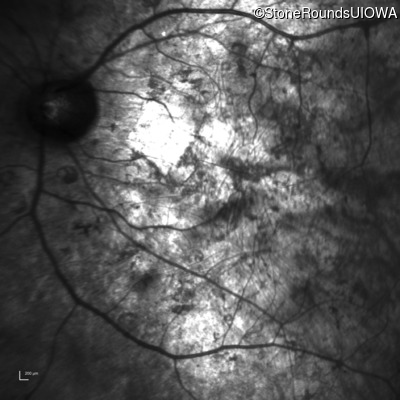

Infrared Fundus Photograph - Right - Hand Motion sc

Exemplar